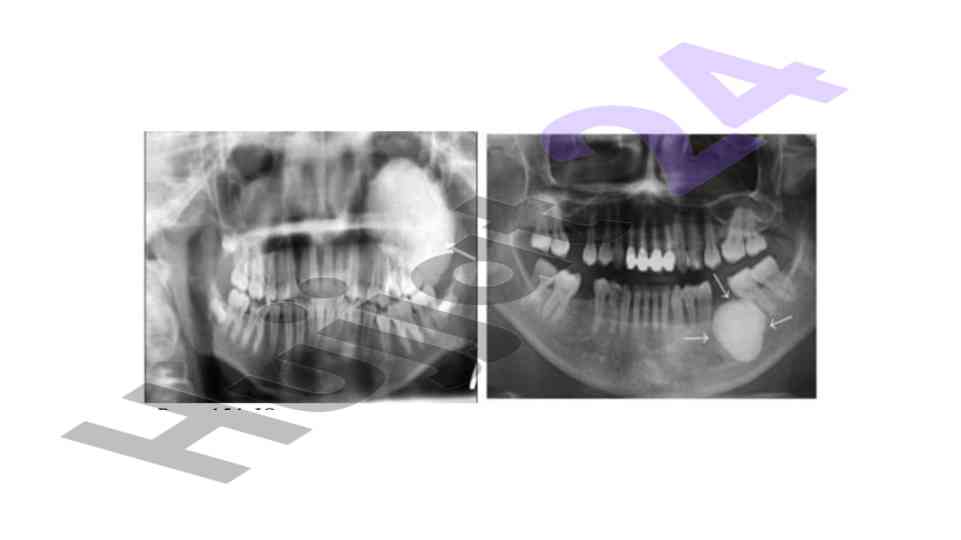

Xavfsiz osteogen o‘smalar klinikasi va davolash

Xavfsiz osteogen o‘smalar, ularning klinikasi, tashxisi va davolash usullari haqida maslahatlar. Osteomalar va ularning turlari detallari bilan.